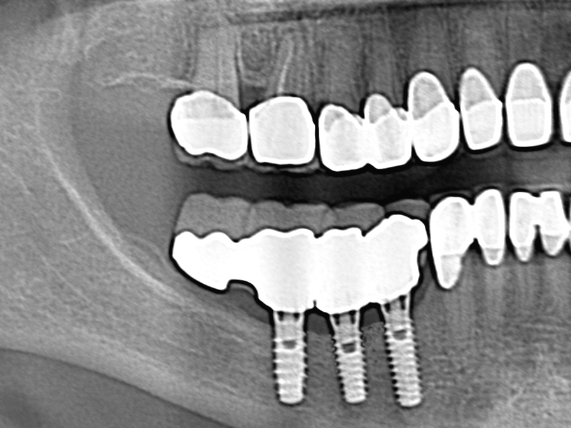

The procedure begins with careful planning. High-resolution CBCT scans are always the first step because they allow the surgeon to measure bone dimensions with millimeter accuracy. During surgery, a small window is made in the side of the jawbone, exposing the nerve canal. The surgeon gently mobilizes the nerve and moves it aside, creating enough vertical space for implants to be inserted in the correct position and angulation. Once implants are placed, the nerve is relocated to rest around them without tension, and the area is secured.

At its core, nerve lateralization involves gently repositioning the inferior alveolar nerve (IAN) to create a safe path for implant placement. This nerve runs inside the lower jawbone and supplies sensation to the chin, lower lip, and some of the lower teeth. When the jawbone in the molar area is too thin or too close to the nerve canal, placing implants can risk nerve damage. Traditionally, patients in such cases might have been advised to opt for short implants, bone grafting, or even removable dentures. However, nerve lateralization has opened the door for fully fixed implant solutions even in severely resorbed mandibles.